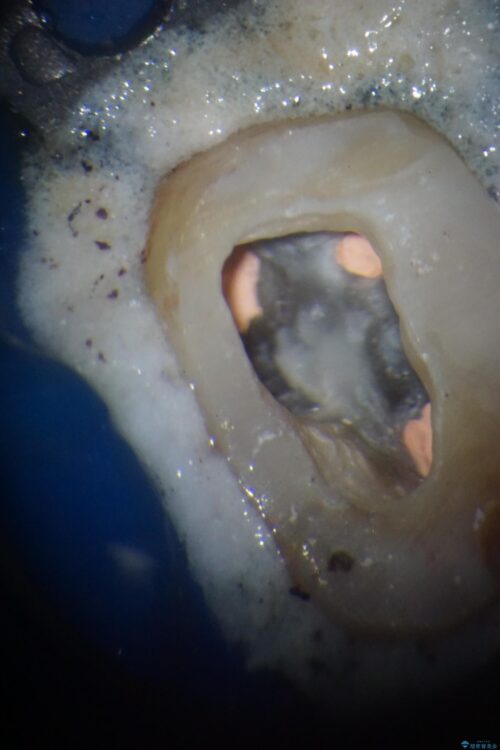

奥歯がズキズキと痛み、食事で噛むことができないとのことで来院された患者様です。 以前治療を受けたとき、むし歯が大きかったため、神経組織が炎症を起こす可能性があると指摘をされていたとのことでした。

レントゲン写真から、神経組織近くにまで大きな修復物が認められました。

叩いたり、冷熱や電気刺激によるテストを行ったりとしましたが、炎症の状態は芳しくなく、根管治療を行う前提で処置を行うこととしました。

初診時は神経組織の生活反応が認められましたが、2日後に処置を行ったときには、既に反応はなくなっている状態でした。

神経組織は壊死が始まっておりましたが、初回処置後には痛みを感じることもなくなり、2回目に無事に根管治療を終えることができました。

治療途中

• 奥歯がズキズキと痛む 奥歯の虫歯治療 治療途中画像